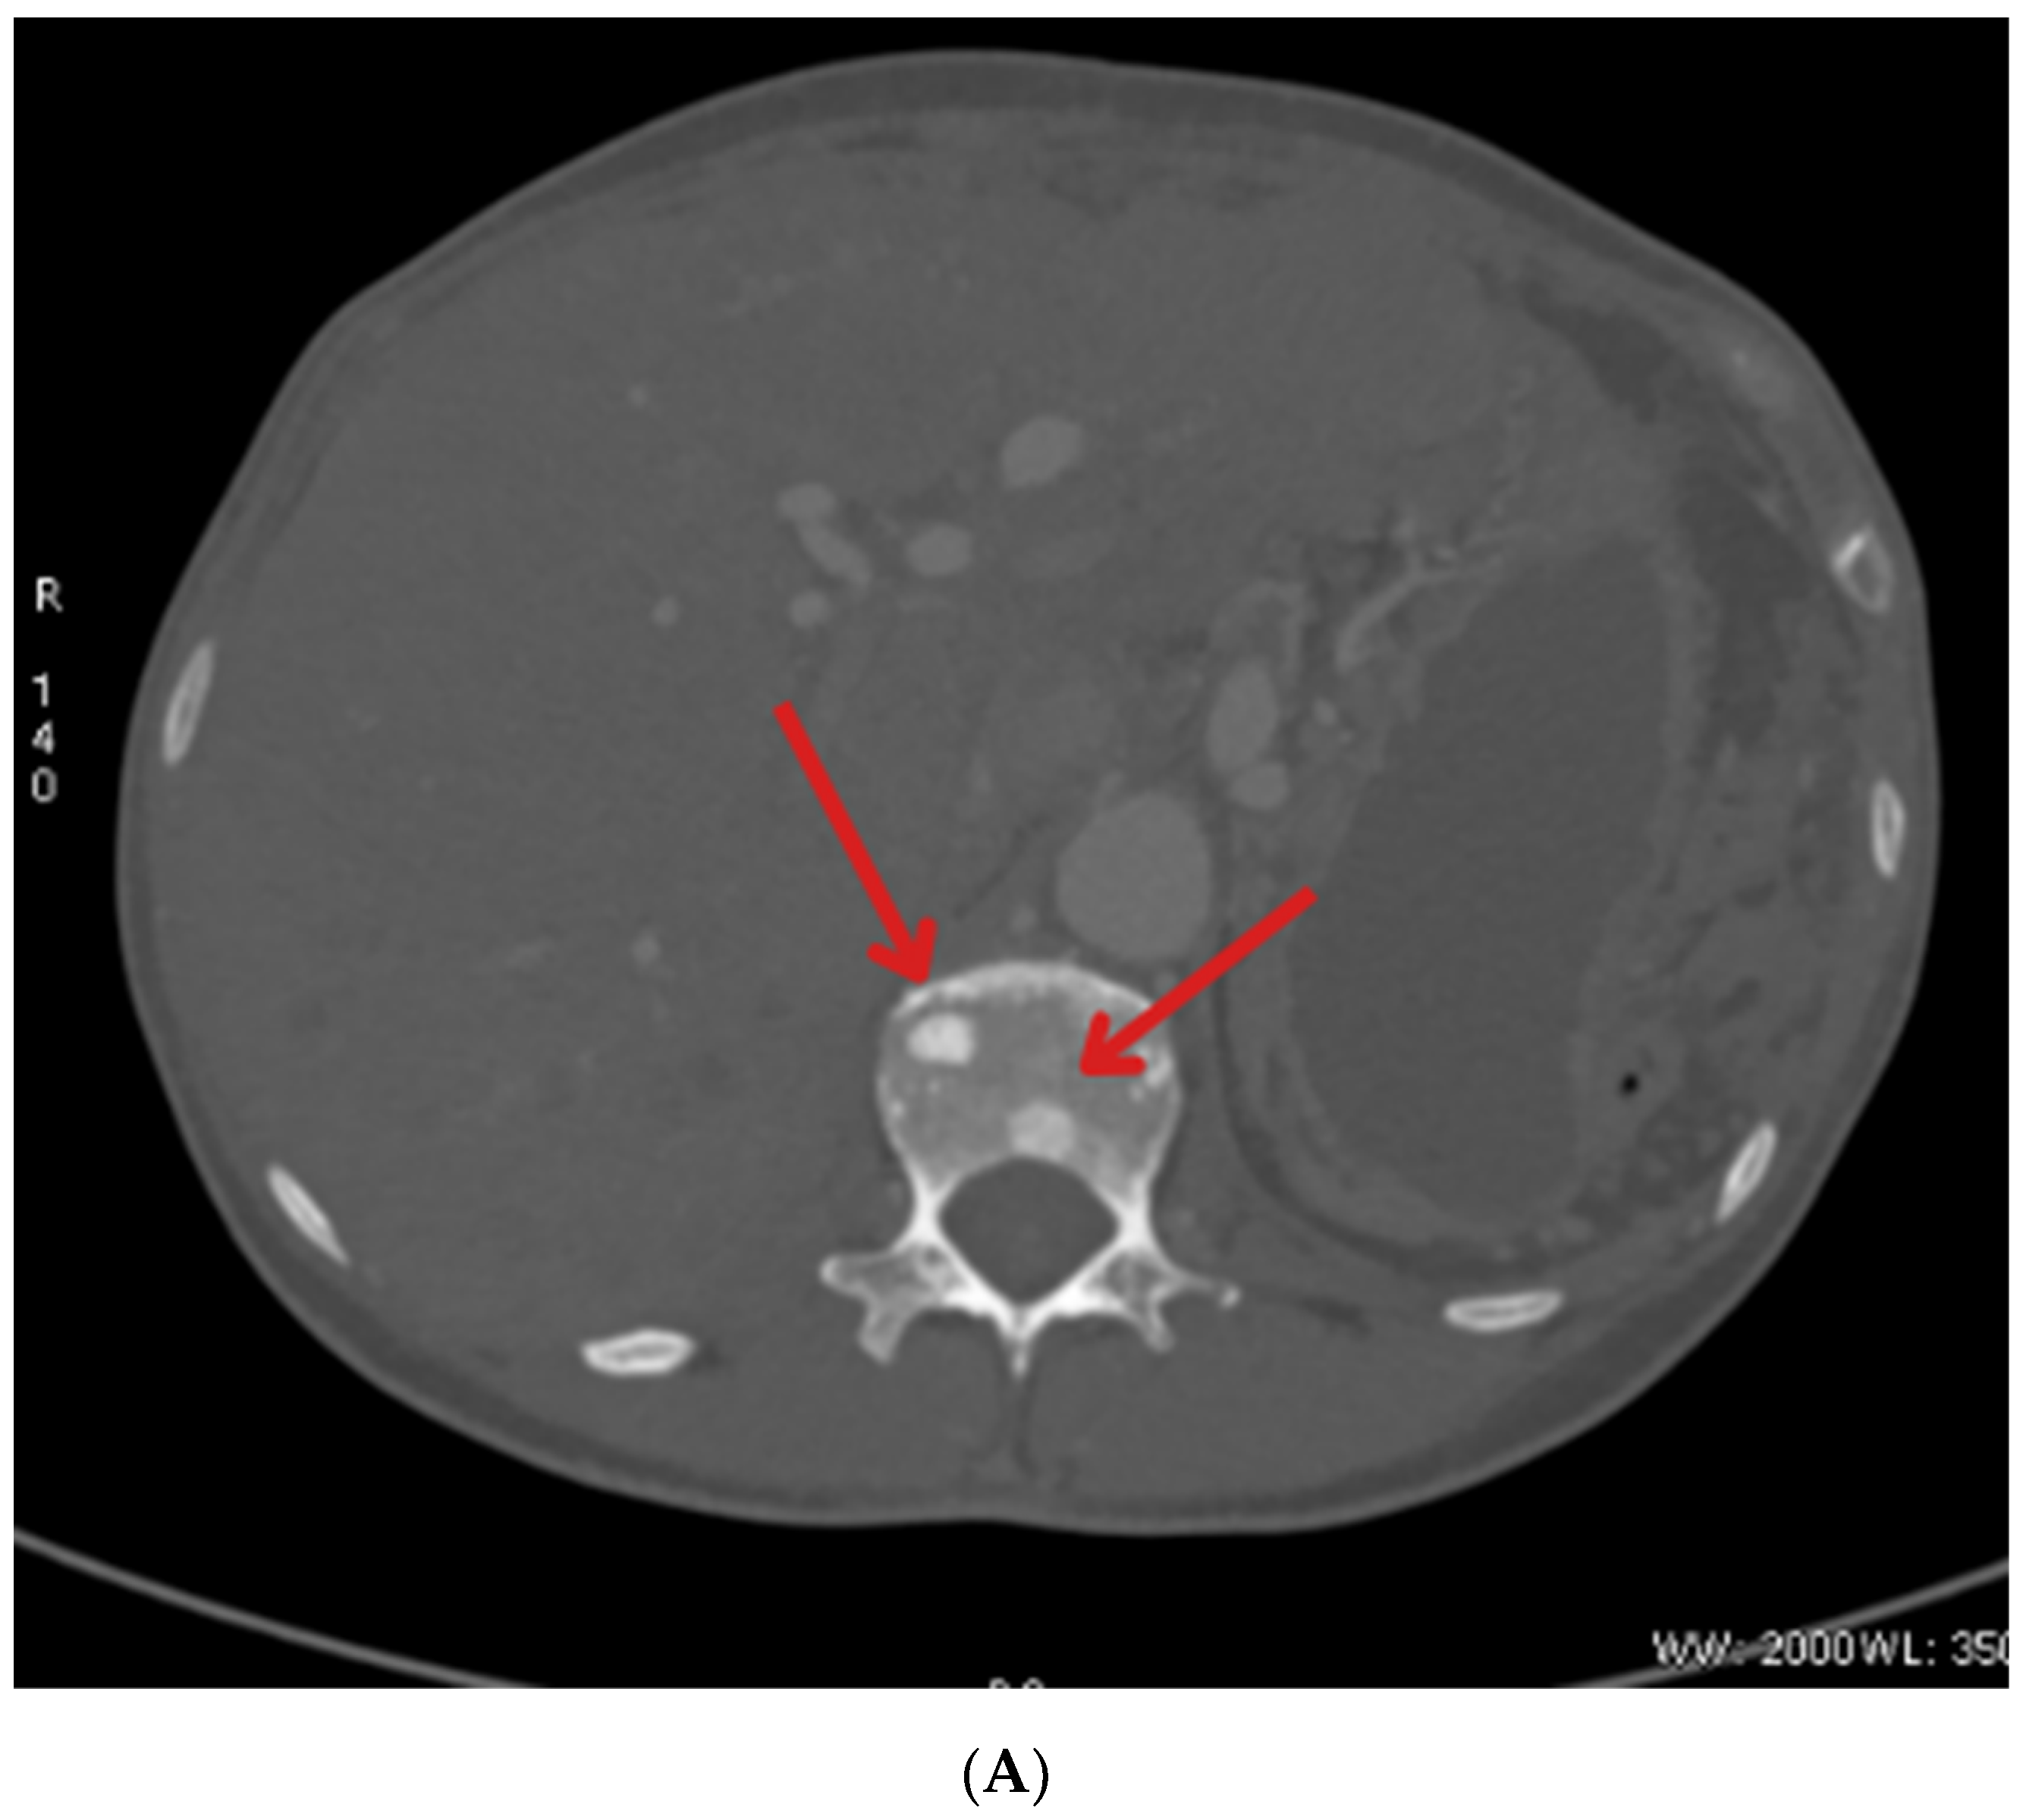

| May 2023 | Beginning of Lutathera treatment CT scan: metastases in the liver, bone sclerosis, enlarged lymph nodes |

| October 2023 | Significant progression of metastases in the liver and bones (spine, ribs, pelvis), and periaortic and pelvic lymphadenopathy The patient was referred to palliative hospice care, resigned from further PRPRT treatment |